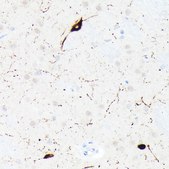

Anti-Somatostatin (SST) Antibody, clone 7Q4T0, Rabbit Monoclonal,

immunohistochemistry: 1:50 - 1:200

The hormone somatostatin has active 14 aa and 28 aa forms that are produced by alternate cleavage of the single preproprotein encoded by this gene. Somatostatin is expressed throughout the body and inhibits the release of numerous secondary hormones by binding to high-affinity G-protein-coupled somatostatin receptors. This hormone is an important regulator of the endocrine system through its interactions with pituitary growth hormone, thyroid stimulating hormone, and most hormones of the gastrointestinal tract. Somatostatin also affects rates of neurotransmission in the central nervous system and proliferation of both normal and tumorigenic cells.

Recombinant fusion protein containing a sequence corresponding to amino acids 23-116 of human Somatostatin (SST) (NP_001039.1).

IHC